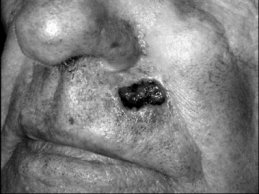

For defects approaching 50% of the vermillion width or greater, a complete vermillionectomy and mucosal advancement flap repair may be performed (Figures 1A–C). By removing the entire vermillion the risk of subsequent malignancy from adjacent actinic cheilitis is lessened, and the uniform repair and scarring help maintain symmetry of the lip. Like other repairs of the perioral area, mucosal advancement flaps should be marked out prior to the injection of local anesthesia. Mucosal advancement flaps are undermined below the level of the minor salivary glands, but above the orbicularis muscle. They are dissected back to a point where there is minimal closure tension at the vermillion border, and then closed by the rule of halves with absorbable and nonabsorbable sutures. While useful for large defects, mucosal advancement flaps have potential disadvantages. Advancement of mucosa to reconstruct vermillion often decreases the anterior-posterior dimension of the lip and can give a more rounded and reddish color to the reconstructed vermillion. Patients also frequently complain of persistent hypoesthesia, and men may note redirection of beard hair upward, causing irritation to the upper lip.

![]() | ![]() | ![]() |

| Figure 1A: Vermillion defect prior to reconstruction. | Figure 1B: Residual dry vermillion is removed (vermillionectomy), and defect repaired with mucosal advancement flap. | Figure 1C: Healed result. |